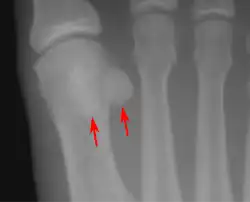

Lateral view.[10]

Bipartite medial sesamoid bone under the first metatarsophalangeal joint of the great toe of the left foot of an adult woman.